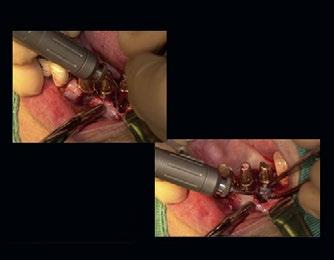

Klinisches Fallbeispiel

Die Röntgenaufnahme wies eine erheb iche Transparenz im Bereich des Implantats nahe Zahn 36 auf. Nach Entfernung der Suprakonstruktion konnten wir feststellen, dass das Implantat sich nicht gelockert hatte. Die Untersuchung ergab, dass sich dieser Fall der CIST-Klasse D zuordnen ließ.

Nach Öffnung einer Klappe stellten wir einen Knochenrückgang und zersetztes Gewebe fest. Dieses Gewebe wurde mit dem Er:YAG-Laser entfernt. Dabei kommt es darauf an, nicht das Gewebe selbst der Strahlung auszusetzen, sondern nur die Schicht, in der geschädigtes und gesundes Gewebe aufeinandertreffen.

Nach Entfernung des kontaminierten Gewebes wurde die oxidierte Schicht des Implantats sterilisiert und abgeschält.